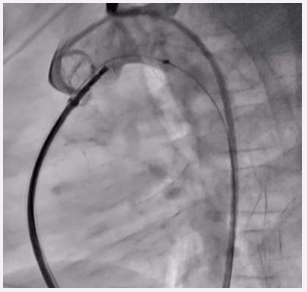

The device was then passed through the defect, and both the aortic and MPA ends of the device were sequentially inflated. A check aortic angiogram showed no residual shunt across the device (Figure 3).

Fluoroscopic image showing the inflated PDA device in situ with no residual shunt across the defect.

Figure 3: Fluoroscopic image showing the inflated PDA device in situ with no residual shunt across the defect.